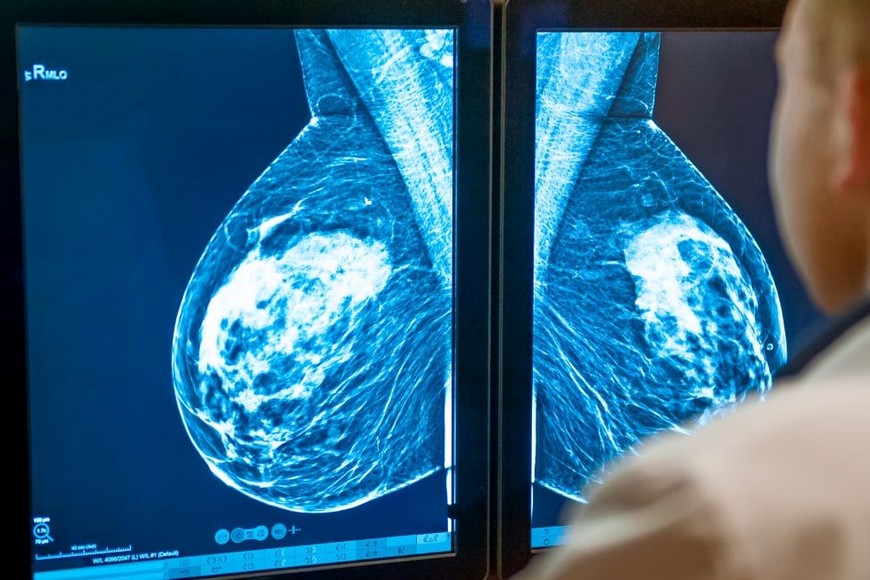

Esta tecnología utilizada en oncología permite obtener diagnósticos más rápidos, precisos y a menor costo.

En el marco del Día Mundial de Lucha contra el Cáncer de Mama, se destaca el avance significativo en la detección temprana de este tipo de cáncer gracias a la implementación de la inteligencia artificial (IA) en el proceso diagnóstico. En Argentina, el uso de software de aprendizaje automático con aprobación de la ANMAT revolucionó la interpretación de estudios de imágenes, acelerando diagnósticos y evitando estudios innecesarios.

Daniel Mysler (MN 72638), miembro de la Sociedad Argentina de Mastología, explica que la IA se convirtió en un "copiloto" tecnológico en la lucha contra el cáncer de mama. Estos programas, respaldados por millones de imágenes validadas, se aplican en mamografías, ecografías y resonancias magnéticas para identificar hallazgos sutiles que podrían pasar desapercibidos. Su aplicación mejoró la precisión diagnóstica y redujo hasta un 30% la realización de estudios, lo que representa un avance significativo en los costos del sistema de salud.

Una vez que el radiólogo detecta una lesión, el sistema realiza un mapeo de las imágenes sospechosas. Mediante el uso de algoritmos inteligentes de aprendizaje automático, se procesa la información y se genera un cálculo sobre la probabilidad de malignidad, clasificando las lesiones estudiadas según el nivel de riesgo que representa cada una.

“La IA trabaja con algoritmos, programas, como cualquier otro que se utilizan a diario, ya sea para viajar, comprar cosas o usar aplicaciones de bancos, etc. Está construido por millones de imágenes validadas que se aplican en una imagen de mamografía, ecografía o resonancia magnética de mama para colaborar en el tamizaje, detectando hallazgos sutiles que pueden pasar inadvertidos o también otorga herramientas para mejorar la precisión diagnóstica del método en cuestión”, explicó el Dr. Mysler.

La sensibilidad de la IA alcanza el 98%, según destacan los expertos, siendo una herramienta crucial para la detección de lesiones que podrían simular benignidad. El profesional resaltó que “esta tecnología permite a los profesionales contar con una opinión instantánea respaldada por estadísticas de sensibilidad y especificidad conocidas”.